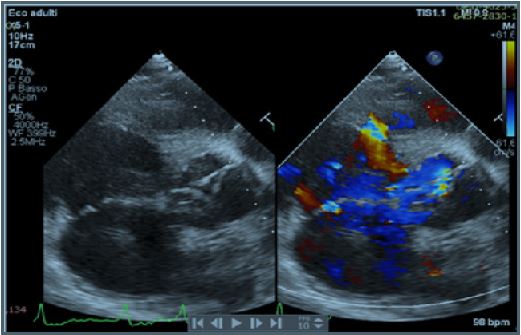

A 42-years old Senegalese man was referred to our department for dyspnea on exertion (NYHA II-III) and clinical signs of heart failure. In his clinical history an undefined cardiopathy, known since childhood but not investigated because asymptomatic, was reported. General examination revealed tachyarrhythmic pulse (rate of 103 per minute) along with normal blood pressure (130/65 mmHg) and arterial oxygen saturation (SpO2 97-99%). Electrocardiography demonstrated atrial fibrillation with left ventricular hypertrophy and signs of pressure overload (Figure 1), while chest X-Ray showed severe cardiomegaly and pulmonary congestion. Transthoracic Echocardiogram (TTE) with color Doppler revealed the presence of a 21 mm perimembranosus Ventricular Septal Defect (VSD), below the aortic valve, with relevant left-to-right shunt (gradient 90 mmHg), partially closed by prolapsing right coronary cusp and accessory tricuspid valve tissue (Figures 2 and 3). A hypertrophied muscle bundle in the mid-ventricular region of the Right Ventricle (RV) along with color-flow turbulence was documented (Figure 4). Due to misalignment, no accurate estimation of intraventricular RV pressure was feasible, but moderate tricuspid regurgitation revealed an atrioventricular gradient of 70 mmHg, suggesting high RV pressures. Other findings were severe aortic valve regurgitation with severe dilation of ascending aorta (diameters of sinuses of Valsalva 60 mm, 28 mm/m2, z-score +6,3, tubular ascending aorta 48 mm, 23 mm/m2, z-score +5,7). 2D and 3 D Transoesophageal Echocardiographic Examination (TOE) confirmed the presence of the anomalous muscle band dividing the RV into two parts: a high-pressure inlet portion and a lower pressure outlet portion (Figures 5 and 6). Severe dilation of both aorta and pulmonary trunk was revealed, confirming severe aortic valve regurgitation with multiple jets and determined by different factors (lack of coaptation, prolapse of the right cusp and distortion of the noncoronary cusp). To accurately measure RV pressures cardiac catheterization was performed. The systolic pressure of the right ventricular inlet and the outlet pressure were 78 and 38 mmHg respectively, determing an intraventricular gradient of 40 mmHg. There was no pressure gradient between the right ventricle outlet tract and the main pulmonary artery (systolic/diastolic/mean pressures were 38/18/25 mmHg respectively). Normal coronary arteries were documented. Patient was scheduled for corrective surgery in the form of resection of the anomalous muscle bundle along with patch closure of the VSD and Bentall procedure for ascending aorta or aortic valve replacement.

Figure 2: Parasternal long axis.

Figure 3: Parasternal long axis.